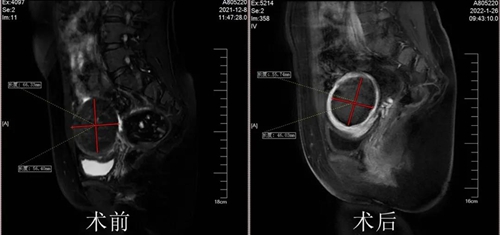

近日,青島婦女兒童醫(yī)院婦科中心迎來了一位亞美尼亞患者Rose(化名)。最近打算備孕的她去醫(yī)院做檢查,發(fā)現(xiàn)子宮內(nèi)長了多個(gè)肌瘤,最大的直徑超過6cm。由于肌瘤病變會(huì)導(dǎo)致受孕難、流產(chǎn)、孕期肌瘤變性等風(fēng)險(xiǎn),因此成了她受孕路上的“攔路虎”……

手術(shù)如期進(jìn)行,經(jīng)過一個(gè)半小時(shí)的海扶治療,有效消融了Rose女士子宮側(cè)壁最大的肌瘤和其他小肌瘤,同時(shí)內(nèi)膜、漿膜沒有一點(diǎn)損傷。看著自己的術(shù)后檢查結(jié)果,Rose女士心里的石頭終于落了地,24小時(shí)后恢復(fù)良好的她順利出院。